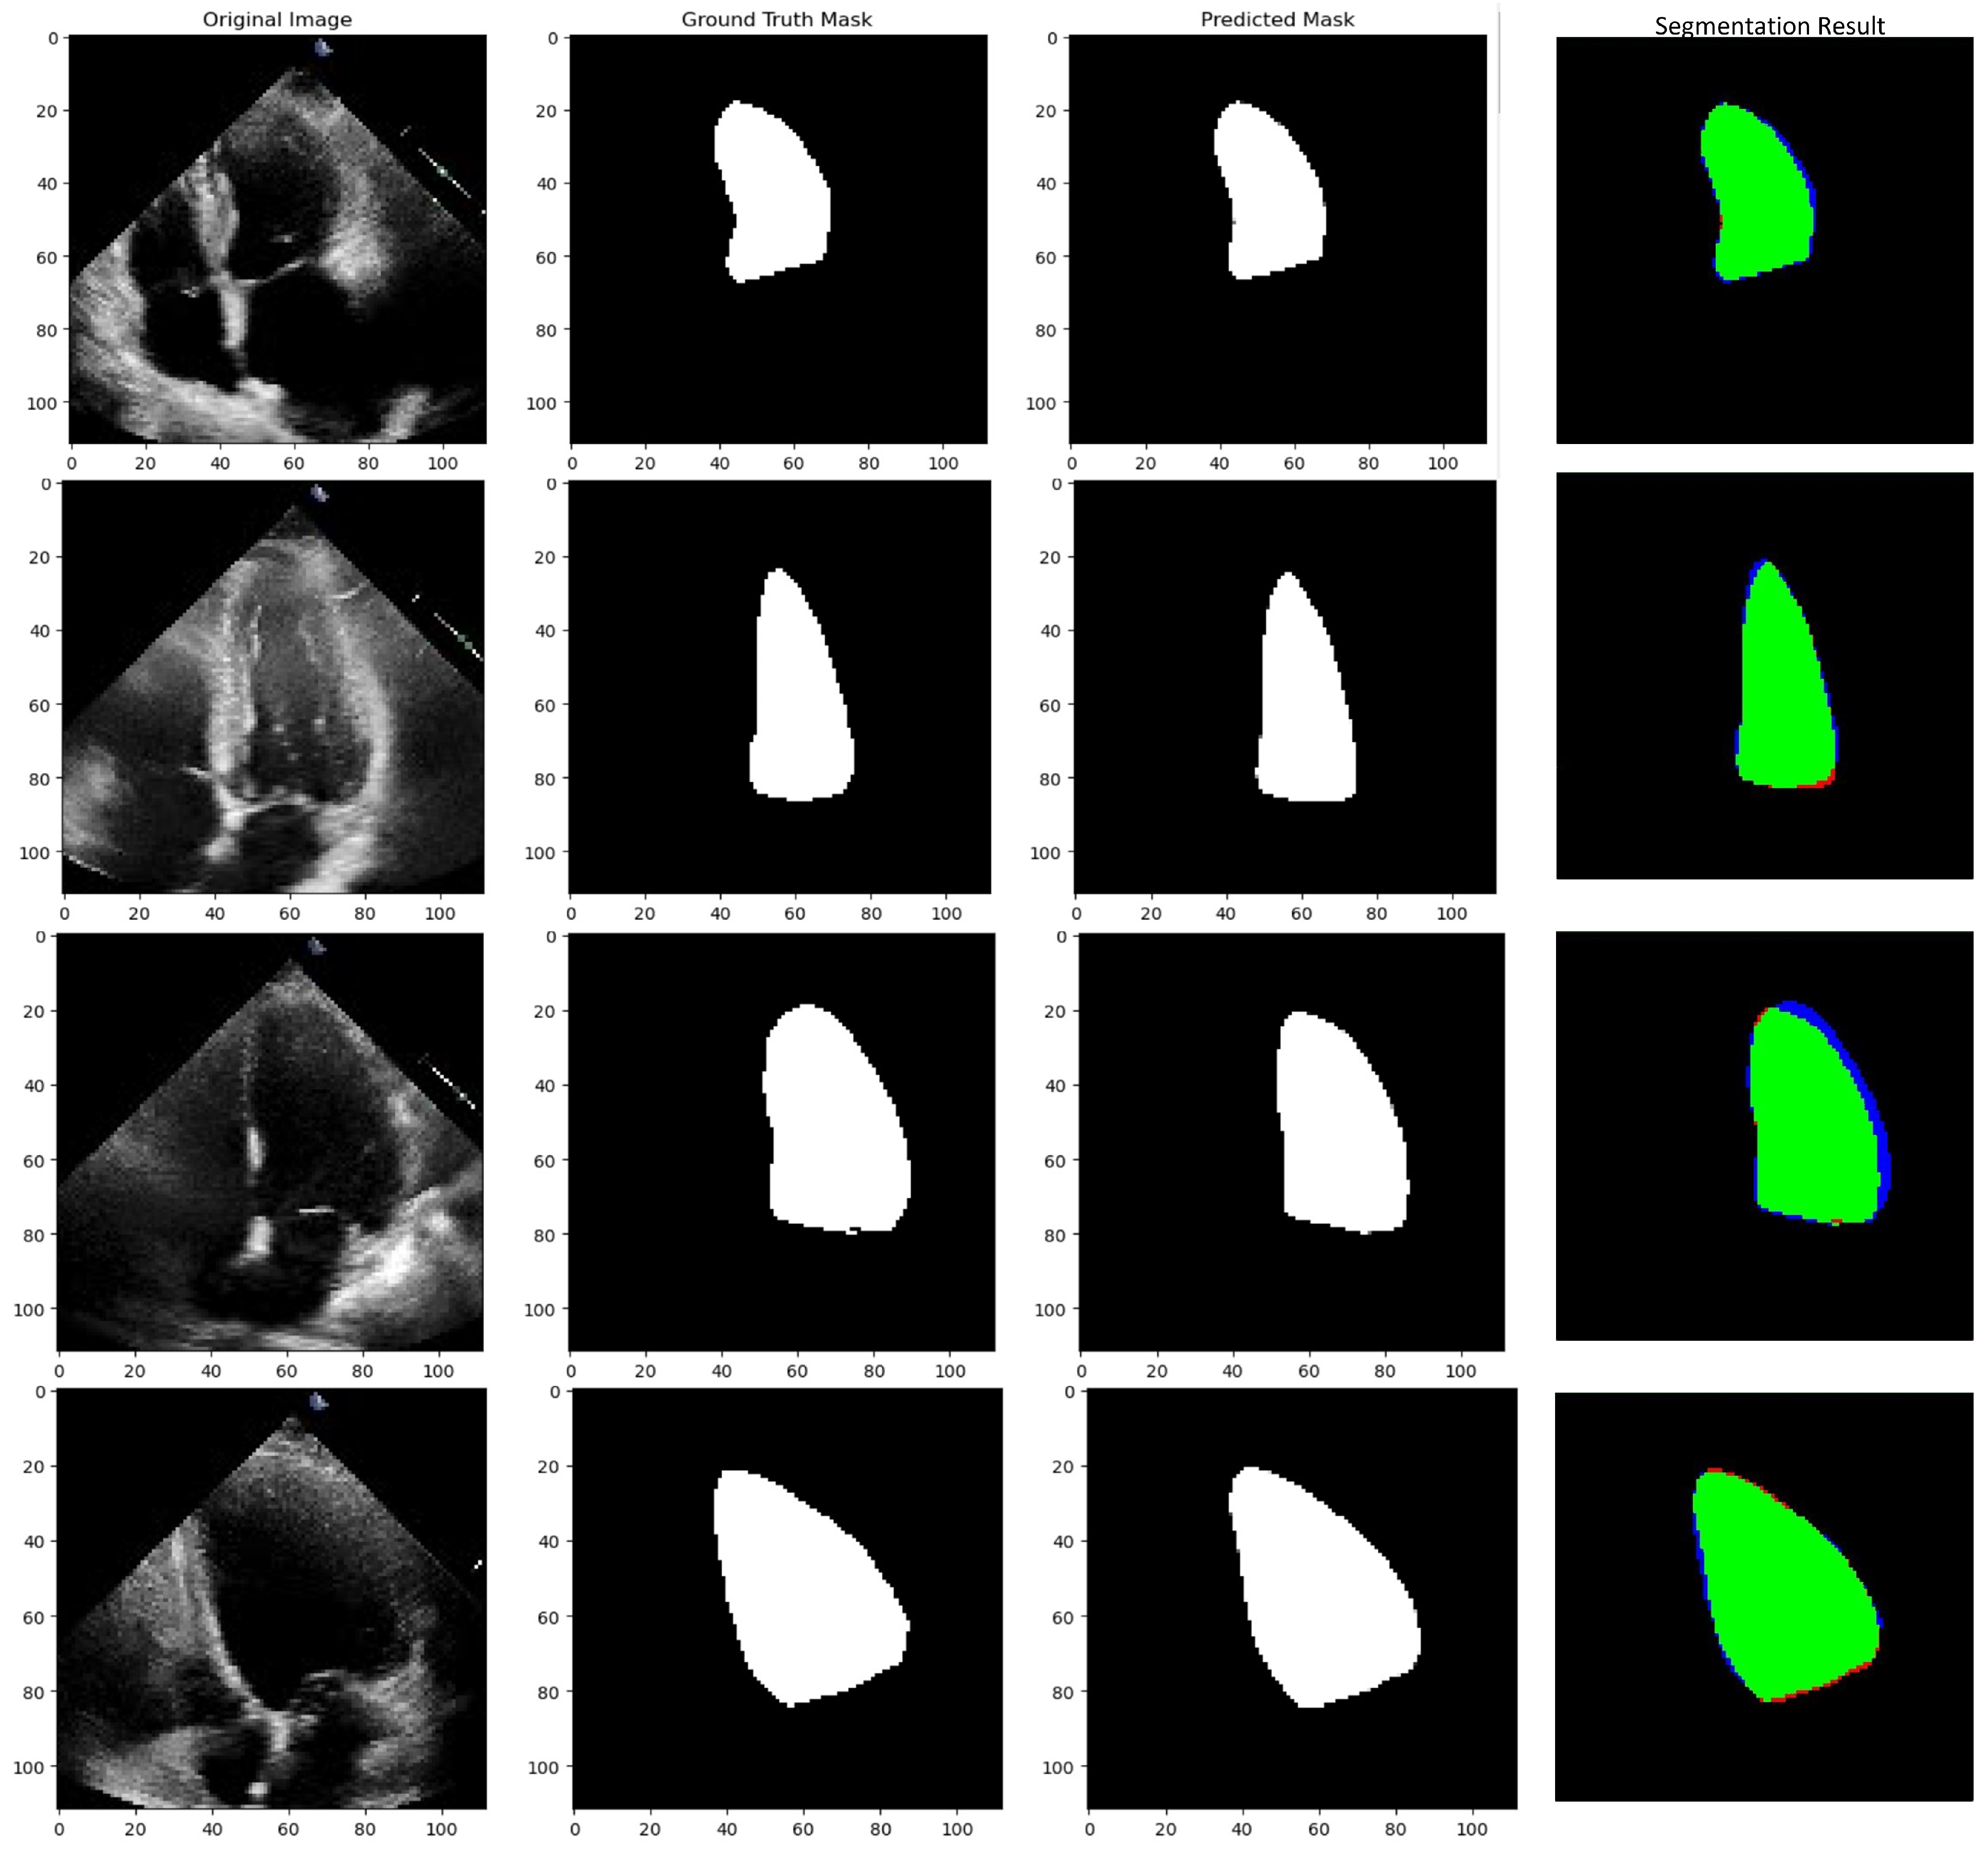

5.3. Implementation Results of Segmentation Architecture

5.3.3. Testing Phase